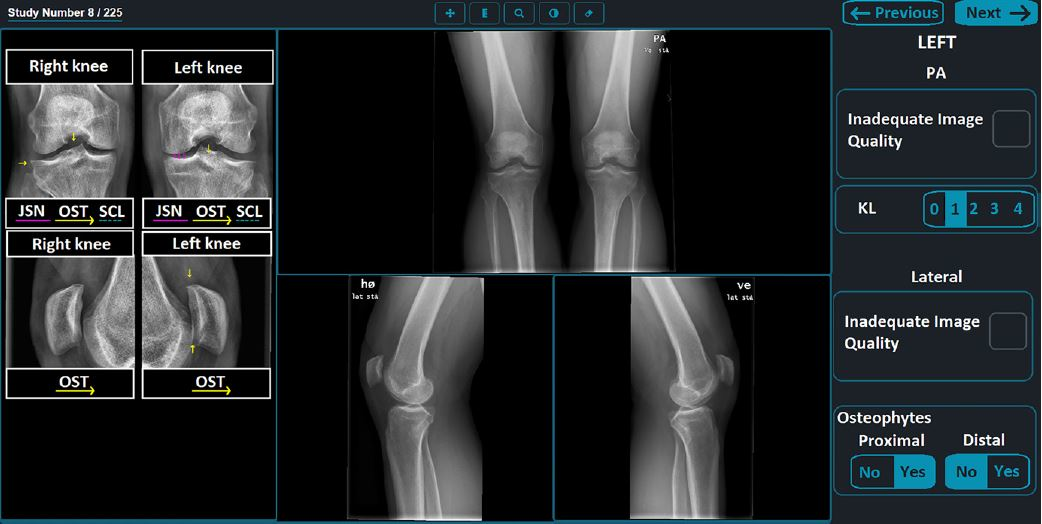

“Multiple-choice formats test only specific knowledge, missing broader clinical complexities,” they wrote. “More nuanced benchmarks are needed to assess LLM skill in radiology, including disease and treatment knowledge, guideline adherence, and real-world case ambiguities. The lack of multimodality in open-source models is a critical shortcoming in the image-centric field of radiology.”